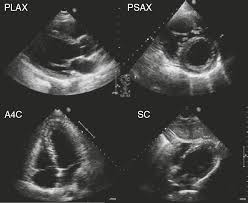

심장 초음파는 인체에 무해한 초음파를 이용해 실시간으로 이러한 심장의 움직이는 모습을 관찰할 수 있고 심장의 움직임과 구조, 혈류의 흐름, 판막의 이상 유무 등을 비침습적으로 관찰할 수 있는 검사법이라고 한다. 대부분의 심장 질환에 필수적인 검사며, 많은 심장질환에서 높은 정확도를 가진다고 한다.

심장 초음파로는 혈액의 역류를 막아주는 4개의 판막이 잘 열리고 잘 닫히는지, 구멍 등 이상 소견은 없는지, 혈액의 역류는 없는지 등을 확인할 수 있다고 한다.

심장 초음파를 통해 심장근육의 손상여부나 좌심실 벽의 두께 등을 관찰해 협심증, 심근경색 등을 알아낼 수 있다고 한다.